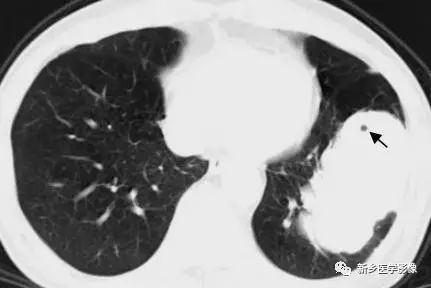

指病灶内1~3 mm大小的点状透亮影,可单发亦可多发。多见于直径在3 cm以下的早期肺癌。其病理基础是尚未被肿瘤组织破坏的肺泡及扭曲未闭的细支气管。

胸部CT肺窗图:显示空泡征(↑)

④.空泡征